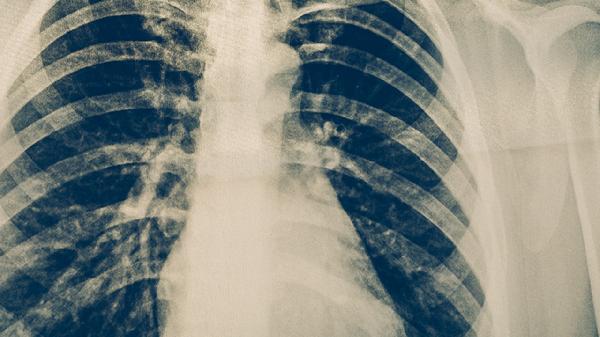

肺结核复发通常可以治好,但需要规范用药和长期管理。肺结核复发可能与治疗不彻底、耐药性结核菌感染、免疫力下降等因素有关,需通过痰培养、药敏试验等重新制定治疗方案。